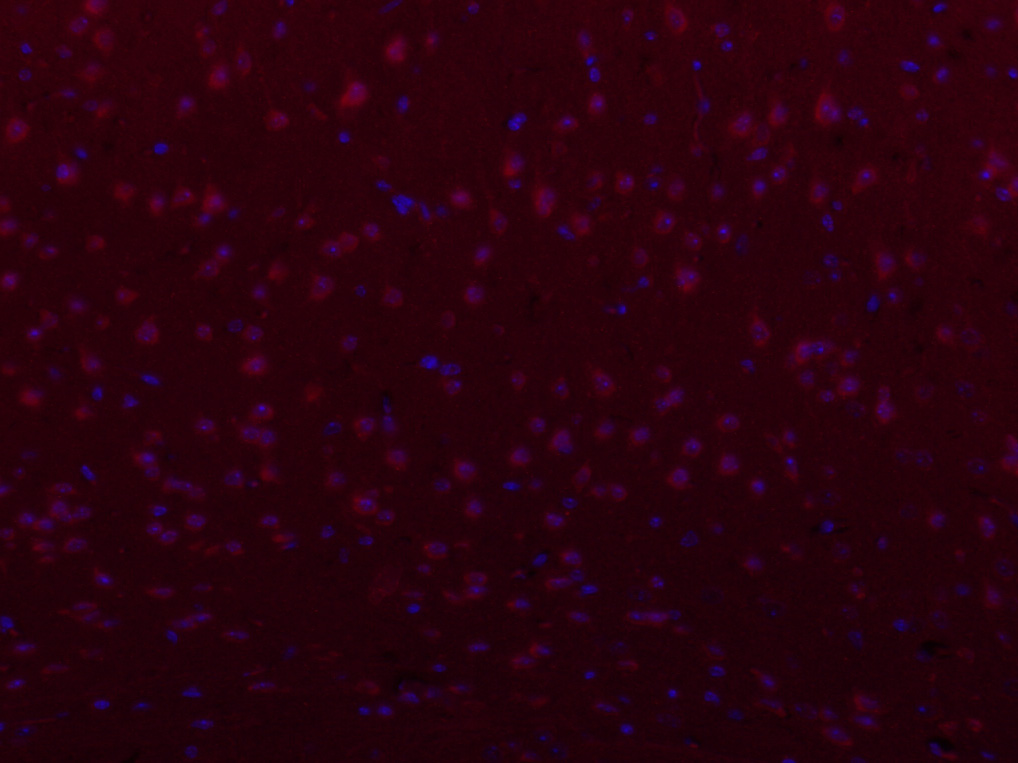

| 英文名称 | PIEZO1 Rabbit pAb |

| 中文名称 | FAM38A/PIEZO1蛋白抗体 |

| 产品应用 | IHC-P=1:100-500, IHC-F=1:100-500, ICC/IF=1:100-500, IF=1:100-500 Not yet tested in other applications. |

| 交叉反应 | Human, Mouse (Rat, Dog, Cow, Sheep) |

| 亚细胞定位 | Endoplasmic reticulum membrane. Endoplasmic reticulum-Golgi intermediate compartment membrane. Cell membrane. |

| 组织特异性 | Expressed in numerous tissues. In normal brain, expressed exclusively in neurons, not in astrocytes. In Alzheimer disease brains, expressed in about half of the activated astrocytes located around classical senile plaques. In Parkinson disease substantia nigra, not detected in melanin-containing neurons nor in activated astrocytes. |

| 功能 | Component of mechanosensitive channel required for the mechanosensitive currents. Plays a key role in epithelial cell adhesion by maintaining integrin activation through R-Ras recruitment to the ER, most probably in its activated state, and subsequent stimulation of calpain signaling. |

| 背景资料 | The protein encoded by this gene is a mechanically-activated ion channel that links mechanical forces to biological signals. The encoded protein contains 36 transmembrane domains and functions as a homotetramer. Defects in this gene have been associated with dehydrated hereditary stomatocytosis. [provided by RefSeq, Jul 2015] |

| {IHC-P} | {1:100-500} |

| {IHC-F} | {1:100-500} |

| {ICC/IF} | {1:100-500} |

| {IF} | {1:100-500} |